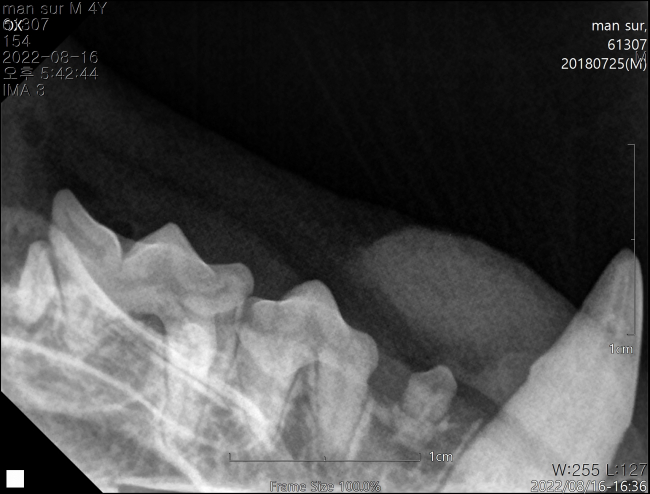

치료전 대상묘

치료중 대상묘